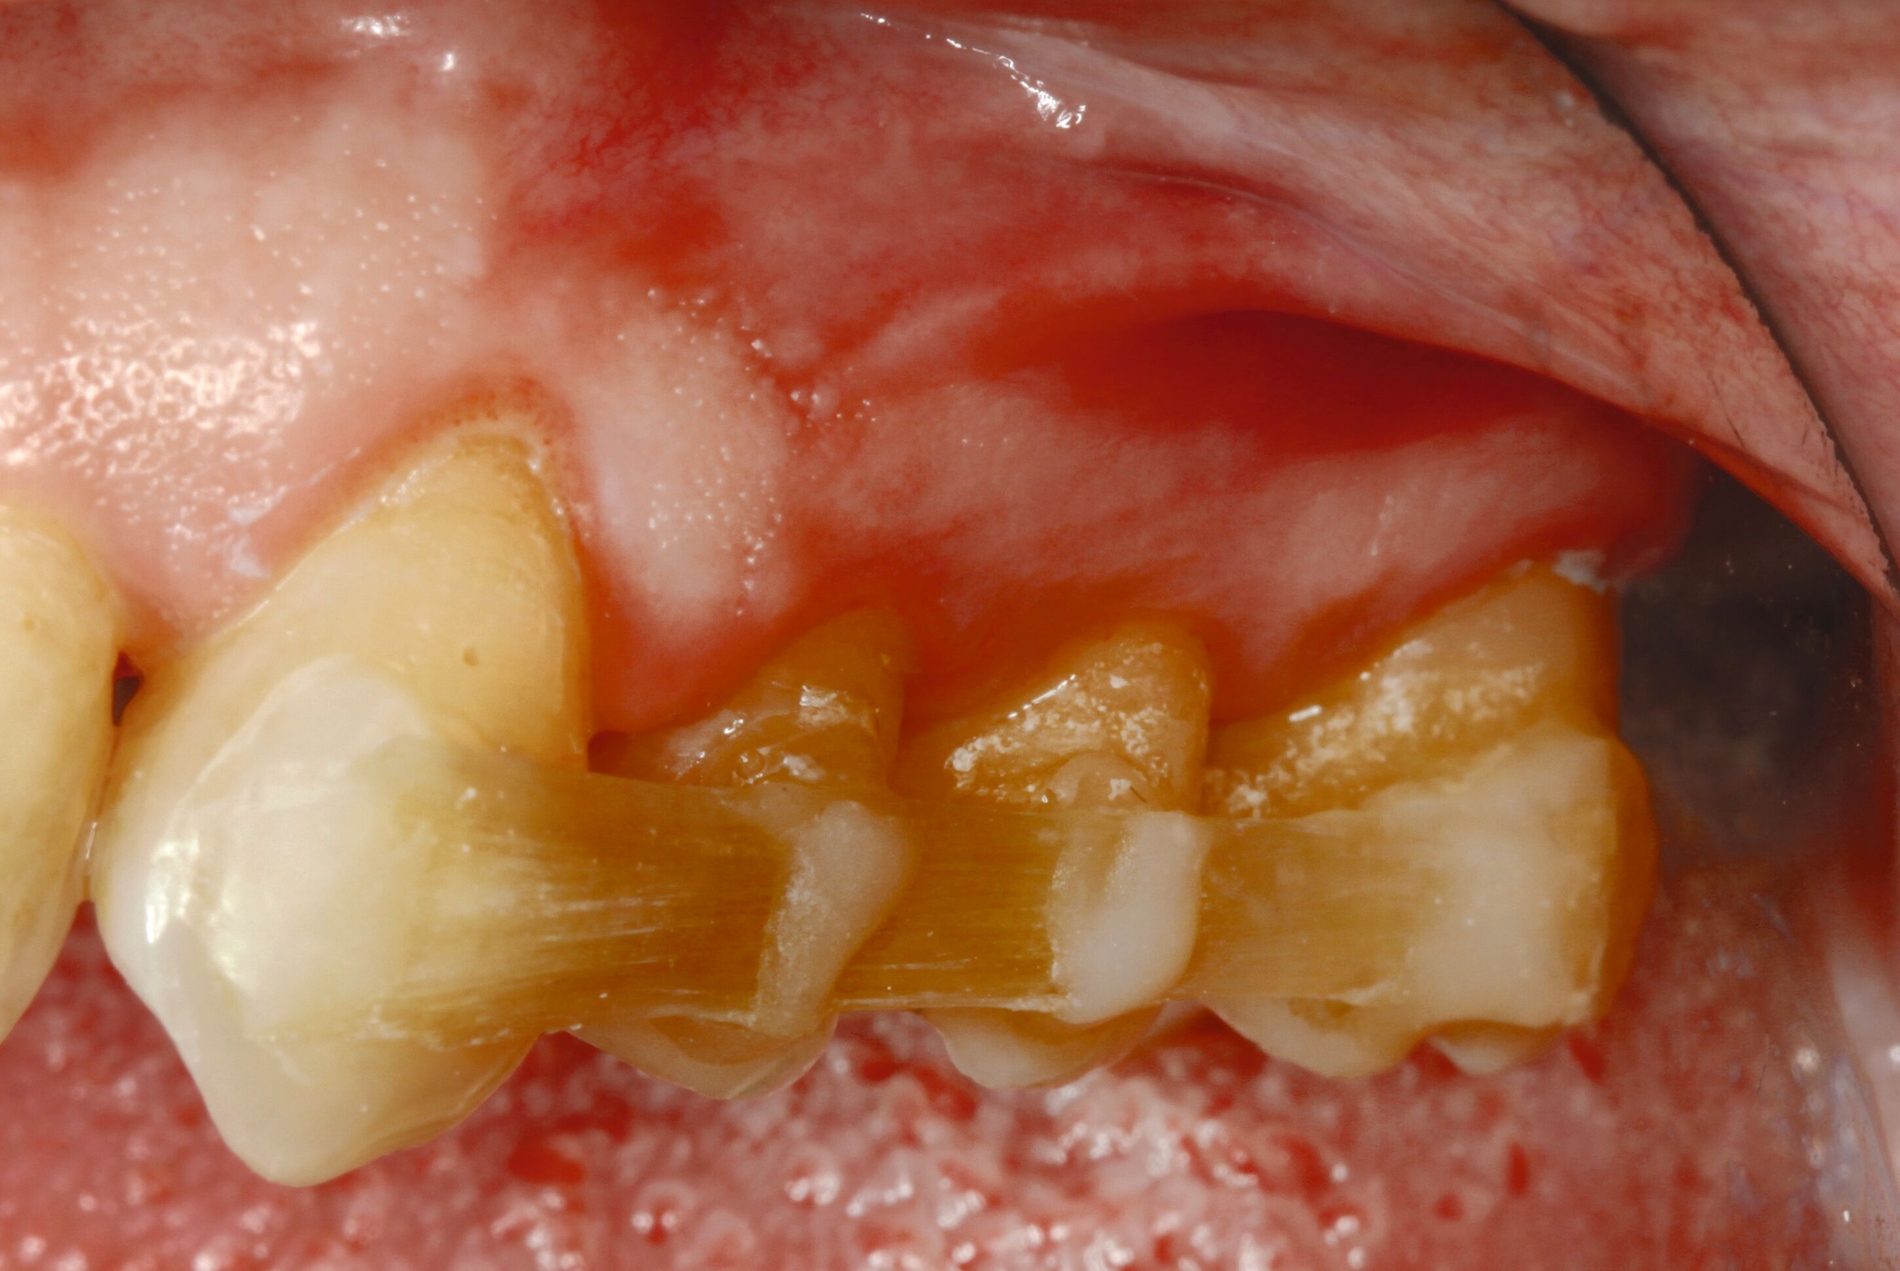

Entsprechend der hier aufgeführten schwachen wissenschaftlichen Evidenz lässt sich schlussfolgern, dass Zähne mit einem Lockerungsgrad II oder höher möglicherweise von einer Schienung vor regenerativen parodontalchirurgischen Eingriffen profitieren können [Cortellini et al., 2001]. Diskutiert wird in diesem Zusammenhang die Förderung der Stabilität des Blutkoagulums durch die Reduktion der Mobilität der Zähne in der Heilungszeit. Nicht zuletzt kann durch eine Schienung das aufgrund der Mobilität mögliche sekundäre okklusale Trauma reduziert beziehungsweise eliminiert werden. In diese Schienungen wird in der Regel jeweils ein benachbarter Zahn ohne erhöhte Mobilität einbezogen. Zwei verschiedene Schienungen zur Reduktion der Mobilität im Rahmen der regenerativen Parodontalchirurgie sind in den Abbildungen 3 und 4 dargestellt.